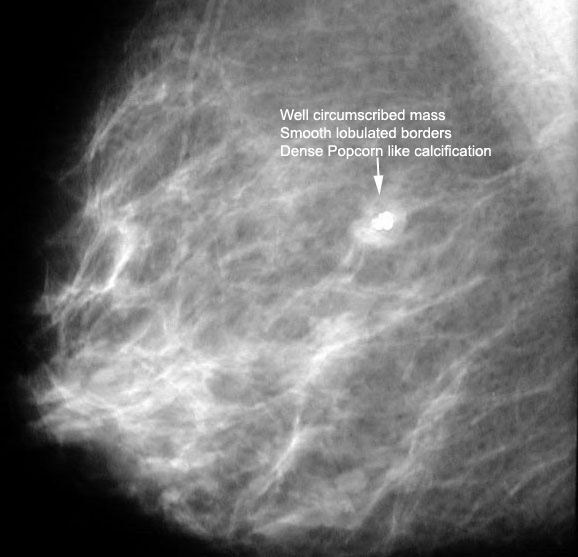

What is the classical appearance of fibroadenomas on mammography?

- A fibroadenoma appears as a well-circumscribed round or oval mass with well-defined borders.

- It may have the appearance of a dense, popcorn-like calcification on mammogram.

Fibroadenoma

35 year old:

Palpable smooth benign type mass. |

64 year old:

Palpable well delineated mass with irregular "pocorn" calcification. |

Q: Fibroadenomas usually have what appearance on mammography?

- A fibroadenoma appears as a well-circumscribed mass.

- Its borders are smooth and round, oval, or nodular.

- They may be multiple and bilateral.